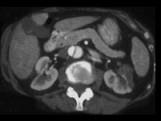

男,54岁,请根据所示图像,选择最可能诊断 ( )A.左侧肾脓肿B.左侧肾囊肿C.左侧肾积水D.左侧肾梗死E.主动脉夹层

问题 男,54岁,请根据所示图像,选择最可能诊断 ( )

选项 A.左侧肾脓肿 B.左侧肾囊肿 C.左侧肾积水 D.左侧肾梗死 E.主动脉夹层

答案 DE